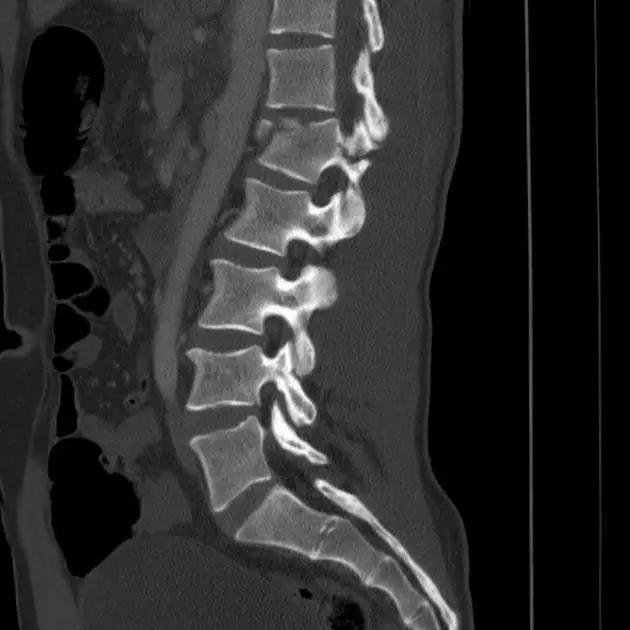

1. Burst 骨折

椎体轴向压力造成的骨折,通常发生骨折碎片向外侧的移位。可以发生在颈椎、胸椎或腰椎。

(来源:Radiopaedia)